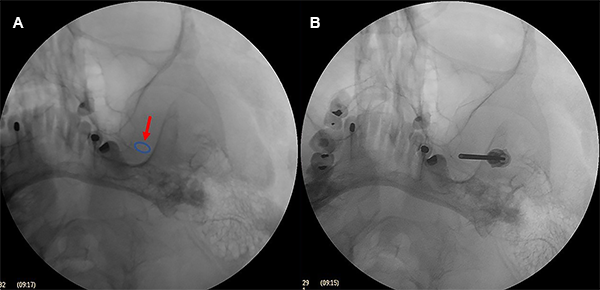

La resonancia magnética de encéfalo fue realizada con una combinación de tres secuencias de alta resolución (3D ponderada en T2, 3D TOF-MRA y 3D T1-Gad) para la detección de un posible contacto neurovascular con cortes finos en los nervios trigéminos. Los agujeros ovales fueron evaluados con radiografías o tomografía computarizada de base cráneo (Figura 2A y 2B).

Figura 2: (A) Radiografía en incidencia de submento-vértical. (B) Tomografía computarizada con reconstrucción 3D de base del cráneo. Las flechas muestran los agujeros ovales.

La aguja guiada de los tres puntos referenciales en la hemicara y bajo control fluoroscópico debe dirigirse a un punto en la línea clival 5-10 mm por debajo del piso de la silla turca o en la intersección del peñasco del hueso temporal con el clivus, hasta que se engancha en el agujero oval. Es innecesario penetrar más allá del agujero. La aguja simplemente permanece en el agujero oval (Figura 5).

Cuando es difícil ingresar al foramen oval se puede obtener una imagen en fluoroscopia en incidencia submento-vertical para visualizar el foramen oval; sin embargo, como esta incidencia es difícil de realizar en una cama quirúrgica, se realizó una incidencia fronto-submaxilar oblicua (Figura 6).

Figura 6: Incidencia fronto-submaxilar. El agujero oval izquierdo se ve medial a la rama de la mandíbula y lateral al maxilar sobre el borde del peñasco.